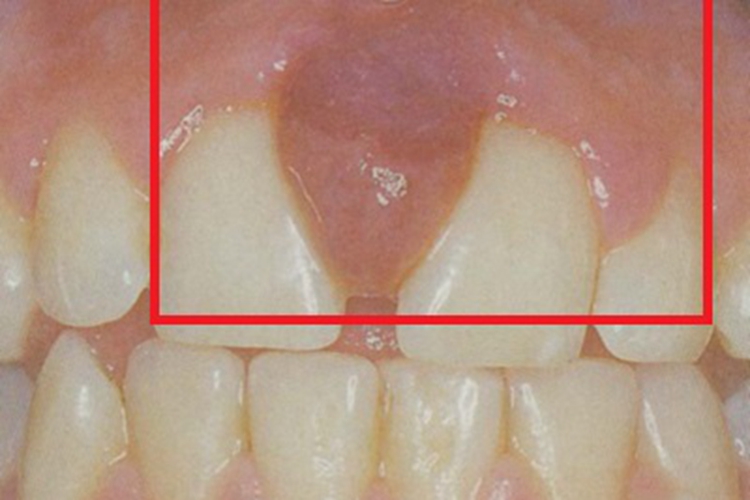

慢性龈炎牙龈肿胀,呈红色改变,表面完整光滑,龈乳头圆钝肥大,可呈肉球状凸起。

慢性龈炎的病损部位一般为牙龈的游离龈和龈乳头,游离龈和龈乳头颜色变为鲜红或暗红色,表面完整、光滑,病变较重时炎性充血、肿胀可波及附着龈。龈缘变厚,龈乳头圆钝肥大,可增生呈肉球状凸起,覆盖牙面。牙龈松软脆弱,缺乏弹性。